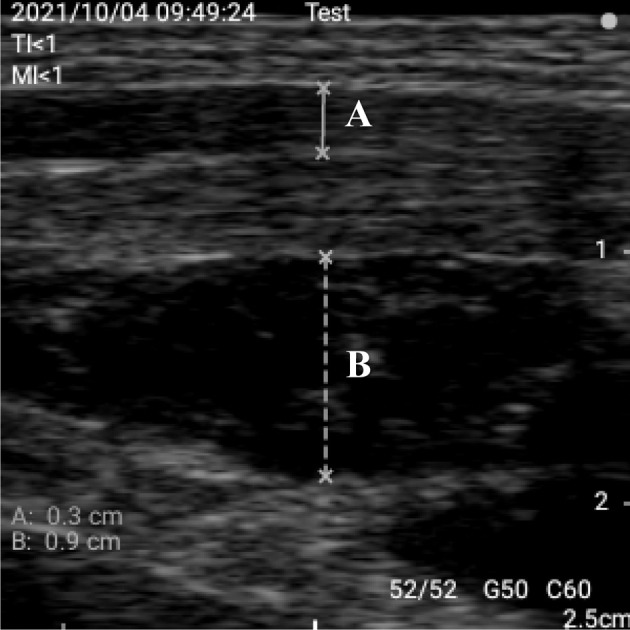

[Purpose] The measurement of muscle mass and thickness to improve preventive care for older adults in community and clinical settings has recently gained attention. Several studies have focused on the thickness of large muscles, such as the trunk and lower limb muscles. However, studies investigating hand muscle atrophy, which hampers daily occupations, are lacking. Therefore, there is a need to measure intrinsic muscle atrophy. This study aimed to investigate the reliability and validity of interdigital muscle thickness measurements using a caliper gauge. [Participants and Methods] This study included 41 healthy young participants. The interdigital muscle thickness was measured in two limb positions with muscle relaxation and contraction using a caliper gauge. Reliability and validity were assessed using the intraclass correlation coefficient and between the interdigital muscle thickness results and other relevant scales. [Results] The results showed high inter- and intra-rater reliability. Additionally, a significant moderate correlation was observed between the interdigital muscle thickness and the other tests regarding criterion-related validity. [Conclusion] Measuring the interdigital muscle thickness using a caliper gauge is a reliable way to evaluate intrinsic muscle thickness. Muscle atrophy between the thumb and index finger is commonly observed in clinical practice. Therefore, measuring muscle atrophy during interdigital muscle thickness or observing finger muscle atrophy may provide useful information in rehabilitation settings.